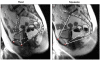

Methods: Pelvic floor anatomy and motion during voluntary contraction (squeeze) and rectal evacuation were assessed by MRI in 64 women with fecal incontinence (FI) and 64 age-matched controls. A radiologist measured anorectal angles and anorectal junction motion. A semi-automated program did the same and also dissected anorectal motion into perpendicular vectors representing the puborectalis and other pelvic floor muscles, assessed the pubococcygeal angle, and evaluated pelvic rotation.

Key results: Manual and semi-automated measurements of anorectal junction motion (r = 0.70; P < 0.0001) during squeeze and evacuation were correlated, as were anorectal angles at rest, squeeze, and evacuation; angle change during squeeze or evacuation was less so. Semi-automated measurements of anorectal and pelvic bony motion were also reproducible within subjects. During squeeze, puborectalis injury was associated (P ≤ 0.01) with smaller puborectalis but not pelvic floor motion vectors, reflecting impaired puborectalis function. The pubococcygeal angle, reflecting posterior pelvic floor motion, was smaller during squeeze and larger during evacuation. However, pubococcygeal angles and pelvic rotation during squeeze and evacuation did not differ significantly between FI and controls.